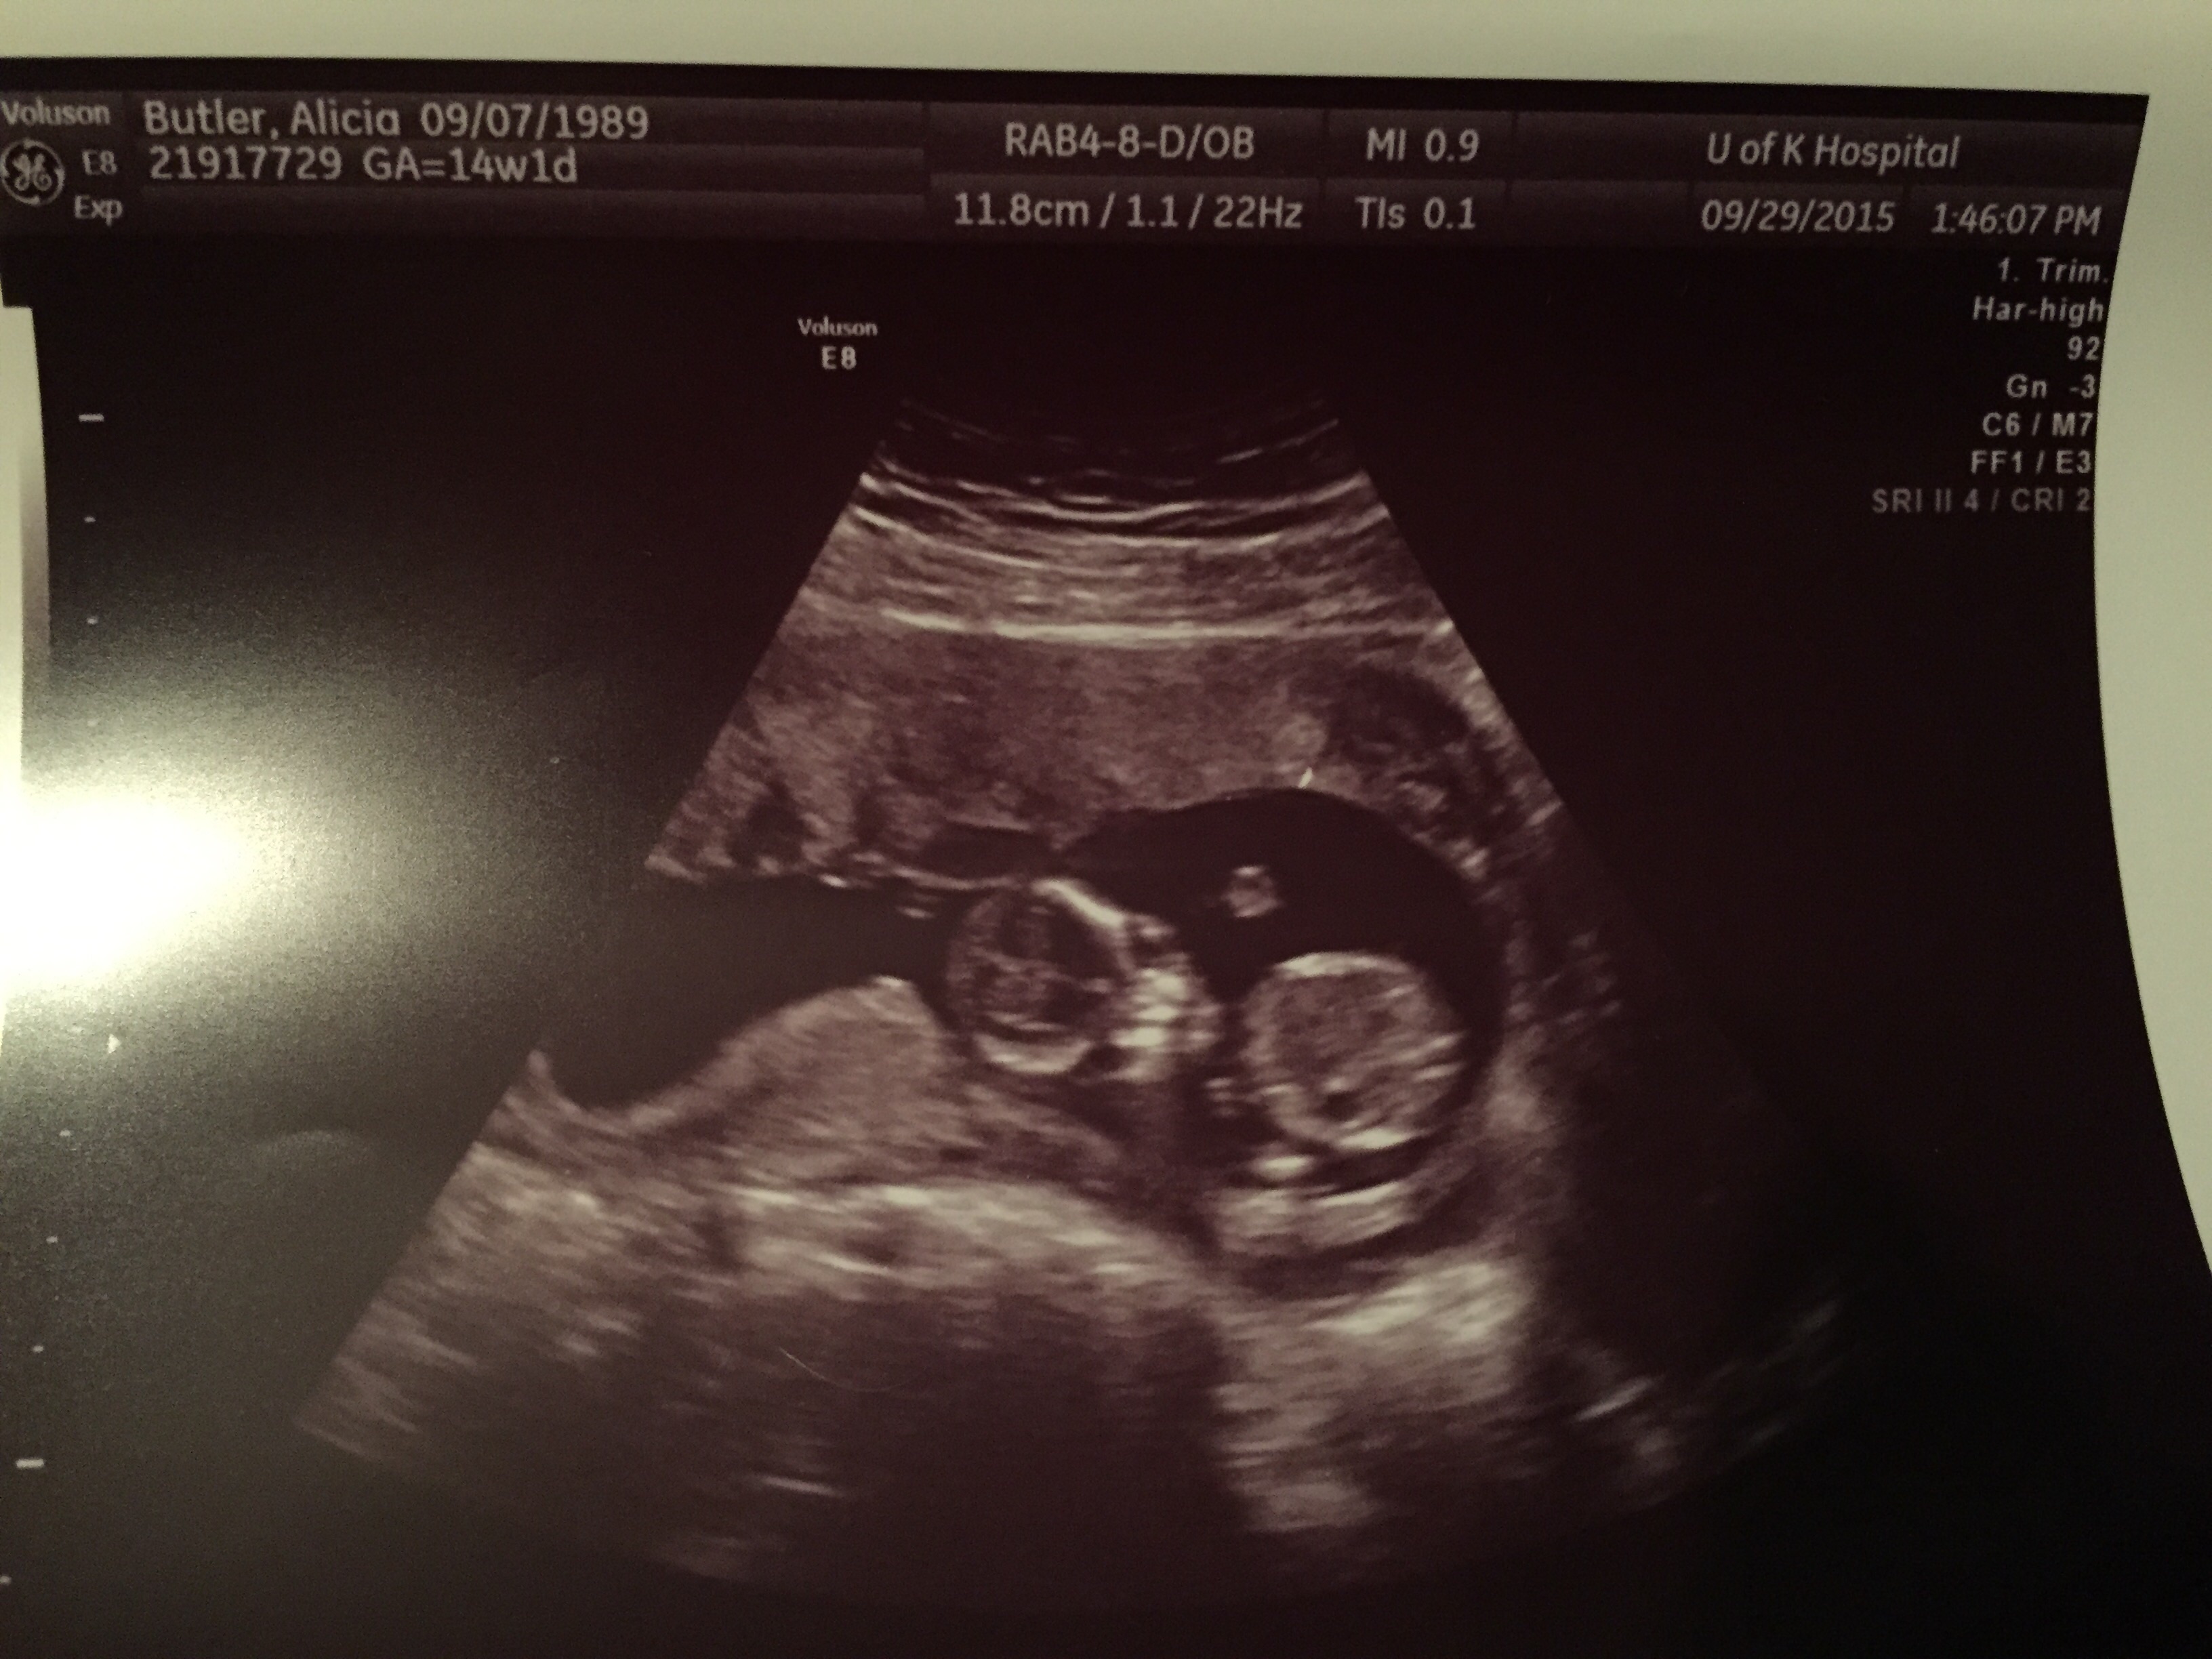

12w 1d today . Wish I would have had one done a little further along to see something more . Fhr at 173 bpm. This is baby #2 we're really stoked

This ultrasound was done at 9w 3d. 12w 1d today . Wish I would have had one done a little further along to see something more . Fhr at 173 bpm. This is baby #2 we're really stoked